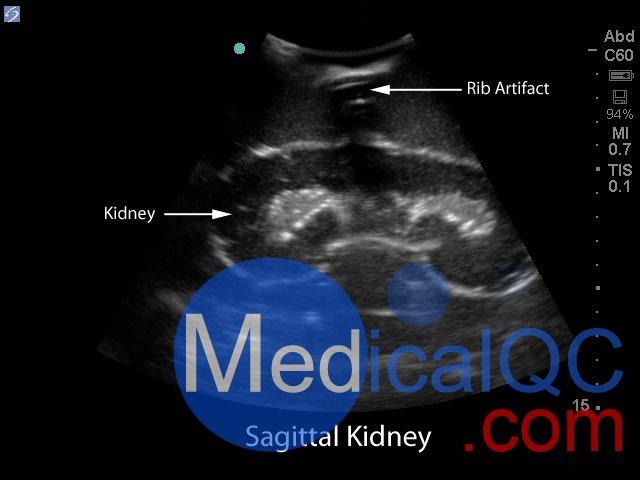

BPRB-2011腎活檢超聲訓練模型,BPRB-2011腎活檢模體非常適合協助臨床醫生熟練使用超聲指導經皮腎臟活檢程序。使用我們極其現實和持久的超聲培訓模型,獲得超聲引導的腎活檢程序的能力和能力。

Blue Phantom的經皮腎穿刺活檢超聲訓練模型允許使用芯針穿刺活檢或穿刺穿刺技術重復進行針頭活檢。該模型提供了解剖學上正確的成年男性軀干,其超聲組織模塊包含皮膚,肋骨和右腎以及周圍組織。腎臟的內部和外部結構在其逼真度和成像特性方面極佳,并且包含腎皮質,腎髓質以及主要和次要的花萼。使用與真實人體組織的聲學特征相匹配的Blue Phantom模擬組織構造而成,因此,當您在我們的訓練模型上使用超聲系統時,您將獲得與在臨床環境中對患者進行成像所期望的相同質量。

超聲成像和程序技能包括;使用超聲系統控制,換能器定位和移動,識別腎解剖結構,在腎活檢期間避免肋骨出現,避免肋骨出現,使用超聲將目標對準腎活檢的適當位置并執行超聲引導的腎活檢程序。使用配置了適當的腎臟活檢換能器的任何超聲成像系統,此超聲動手訓練模型將表現良好。這種超聲體模模型非常適合包括腎臟科,介入放射學,外科手術,外科手術訓練計劃,超聲訓練計劃,模擬中心,外科技能中心,醫學教育設施,腎臟活檢設備制造商和超聲制造商進行超聲教育和演示的專業。

具有包含皮膚,肋骨和右腎以及周圍組織的超聲組織模塊,解剖學上正確的成年男性軀干

腎臟的內部和外部結構在其逼真度和成像特性方面極佳,并且包含腎皮質,腎髓質以及主要和次要的花萼

出色的超聲成像特性:超聲成像特性極為逼真,感覺就像真實的人體組織

超聲組織與真實人體組織的聲學特性相匹配,因此,當您在我們的訓練模型上使用超聲系統時,您將獲得與臨床環境中對患者成像相同的質量